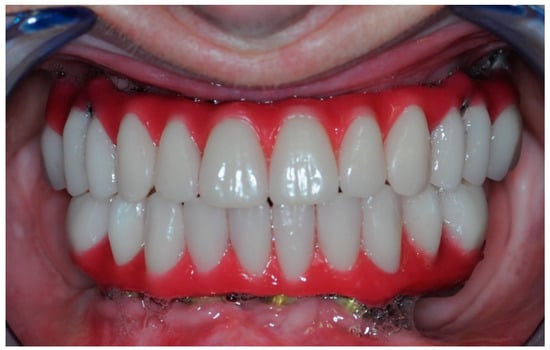

2.5. Final Prosthesis

3.5. Function and Aesthetics